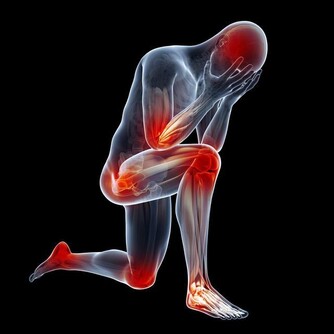

許多患者只有血清尿酸鹽濃度的增高而沒有臨床症狀,只有在發生關節炎時才稱為痛風。痛風的病理基礎是高尿酸血症,正常人血尿酸值是男性2.4-7mg/dL,女性1.6-5.2mg/dL。

當體液中尿酸濃度超過此值時,將因過剩而在組織中沉積,這種尿酸鹽的結晶沉積在關節滑膜、關節骨、軟骨而導致痛風性關節炎,沉積在皮下則形成痛風石。中西醫均會要求痛風患者不可以攝取高普林食物,然而這些食物可以說是最起碼的美食,要痛風病患完全不吃這些食物,說真的,這種治療的犧牲代價還不小呢!

嘉眾草師表示,許多人耽心椰子會不會太涼?其實這是多慮了,因為患有痛風的人,本身體質會偏燥,高普林會不斷累積,椰子水正好可以清洗積存的痛風石,這是西藥秋水仙很難做到的。痛風的確是一種令病人非常痛苦的一種病症,當它發作的時候,可以說是「痛不欲生」,這種毛病還真會整人,它發作時間通常是選擇在夜深人靜的時刻。